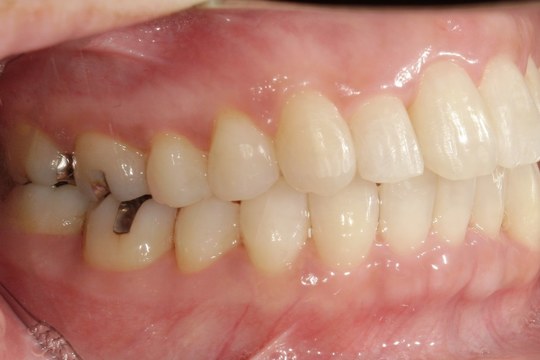

Y.S. 30代男性

全体的にガタガタしているのが気になるという主訴だったため、上下左右第一小臼歯を抜歯し、叢生を並べました。

治療の期間:R3. 9/1〜R5. 10/31

治療の価格:88万円